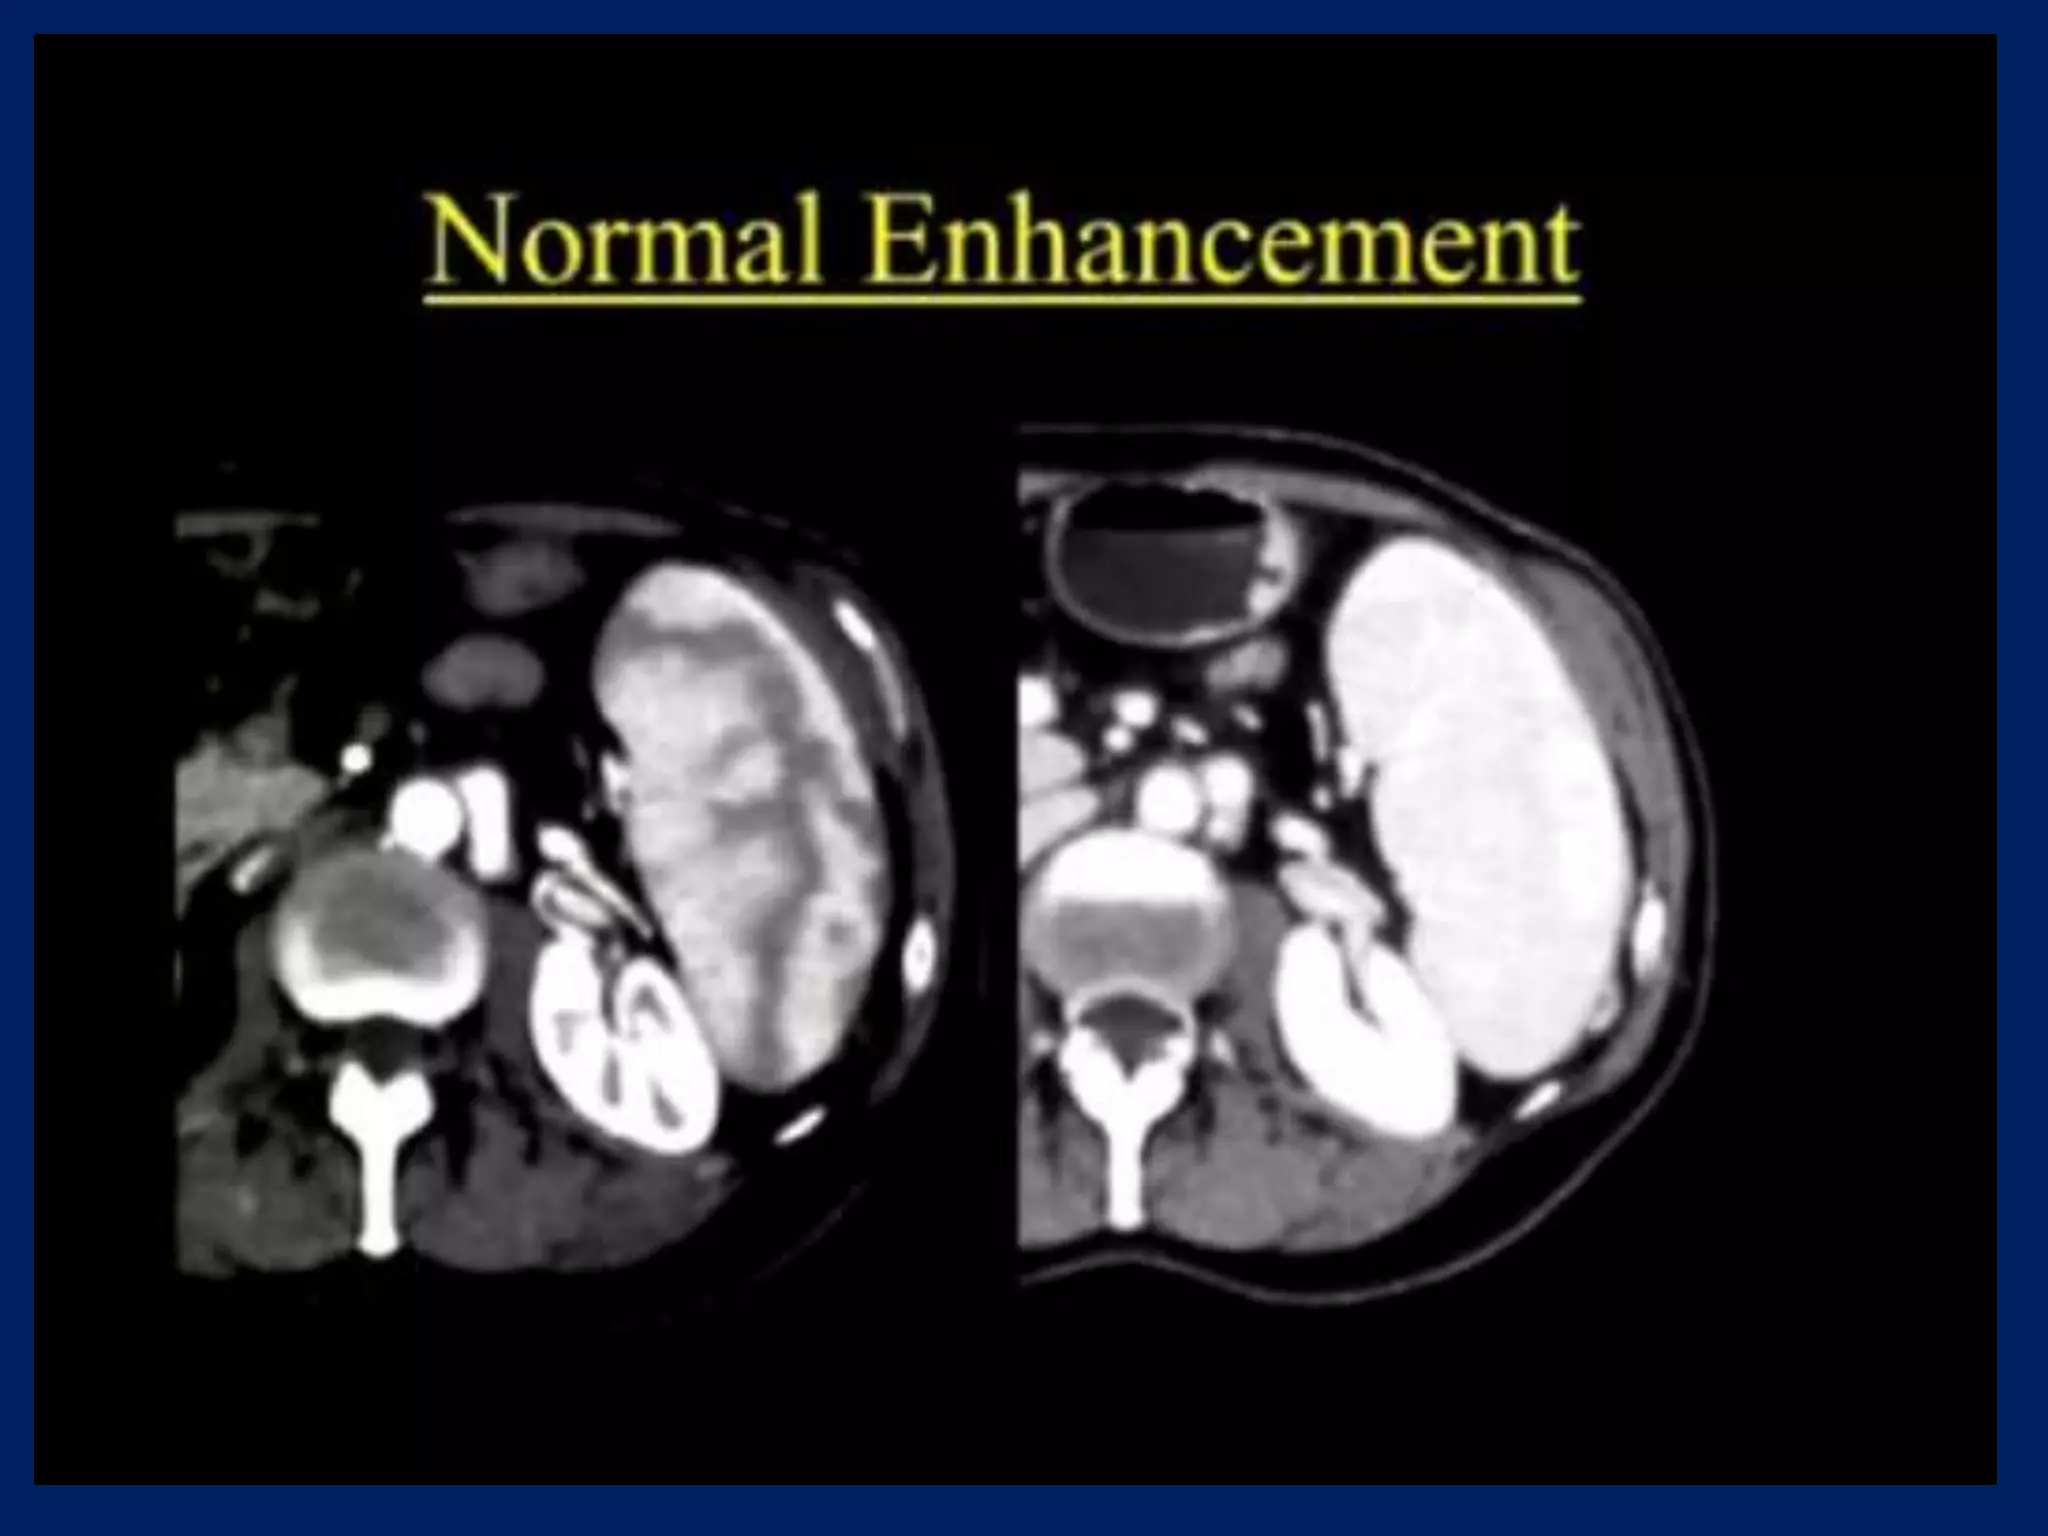

This document discusses imaging of the spleen and summarizes various congenital anomalies and pathologies that can affect the spleen. Some common congenital anomalies mentioned include accessory spleens, asplenia, polysplenia, and splenic fusions. Acquired conditions like repeated infarctions, infiltration, tumors, and cysts can also cause splenomegaly or functional asplenia. Wandering spleen is discussed as a rare congenital anomaly where the spleen lacks attachments and is mobile within the abdomen. Various grades of splenic lacerations and examples of splenic imaging findings are also briefly summarized.